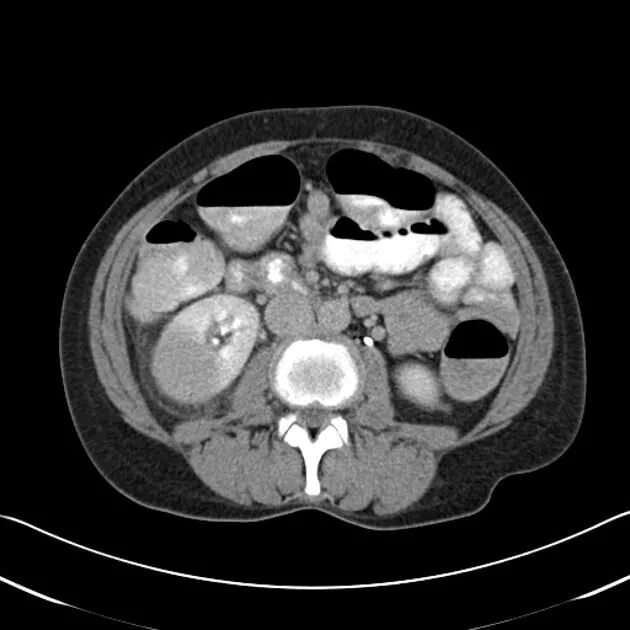

Пиелонефрит кт